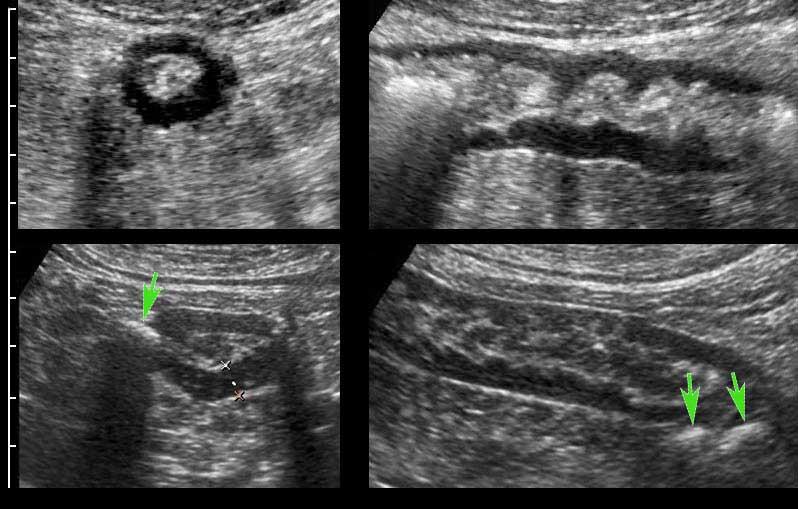

Intussusception

Đây là hình ảnh siêu âm của một trẻ 2 tuổi bị lồng ruột hồi manh tràng từng đợt, được khám trong khoảng thời gian giữa các cơn.

Hồi tràng với nhiều mảng Peyer sa vào manh tràng.

Hình ảnh siêu âm kinh điển của lồng ruột hồi-manh tràng ở hai trẻ khác nhau.

Trong cả hai trường hợp, đoạn hồi tràng bị lồng được định vị không đối xứng bên trong ống lồng ngoài, do mạc treo ruột tăng âm có chứa mỡ, bám vào hồi tràng và đi theo hồi tràng khi bị kéo vào trong.

Trong mạc treo, siêu âm cho thấy một hạch bạch huyết mạc treo (hbh) phóng đại ở cả hai.

Các hạch này phì đại như một phần của tình trạng tăng sản hạch bạch huyết toàn thân và khônghu trú trong lòng hồi tràng.

Do đó đây không phải là điểm dẫn đầu nguyên phát. Ở bệnh nhân bên phải, ruột thừa (mũi tên) cũng bị kéo vào trong.

Lưu ý cấu trúc đa lớp của thành bụng phía trước của phức hợp lồng ruột, đại diện cho ba lớp thành ruột bị gấp lại.